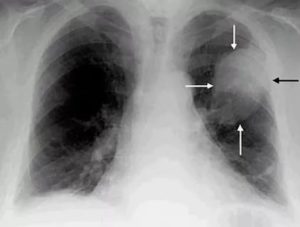

Выглядит рак на рентгеновском снимке как затемненное пятно. Внешний вид злокачественных опухолей может быть различным в зависимости от формы заболевания, стадии ее развития и других факторов. Составляя описание, врач обращает внимание на локализацию теней. По этому признаку заболевание определяется как центральный или периферический, перибронхиальный или бронхоальвеолярный тип.

Признаками центрального рака легких на рентгене служат очаговые единичные (в редких случаях многочисленные) затемнения — зоны инфильтрации, вблизи которых присутствует ткань с признаками компенсаторной вентиляционной функции. Это проявляется в виде более светлого по окрасу ореола, окружающего тень.

Локализация центрального рака в толще органа, обычно в верхних или средних сегментах. Форма опухоли на снимке определяется как негомогенная лучистая: края новообразования неравномерно «расползаются» в стороны. Также рентген выявляет дополнительную тень в области корней, по форме напоминающую сосудистый рисунок.

При плановом обследовании рентген может показать опухоль непосредственно в стенке бронхов — перибронхиальный рак. От других форм заболевания его отличает ограниченность стенками бронхиального древа: злокачественные клетки практически не выходят за их границы. Так как газообмен в пораженных бронхах ухудшается, такая форма онкологии сопровождается сопутствующими изменениями:

- гипервентиляцией — на рентгене видны чрезмерно «завоздушенные» области;

- стенки бронхов выглядят более толстыми и плотными, но края их нечеткие;

- от корня к краям органа пролегают затемненные тяжи.

Признаки воспаления при этой форме заболевания отсутствуют. Неприятных симптомов может не быть.

Наличие опухоли на задней стенке легких Периферическая форма рака Полостная форма рака